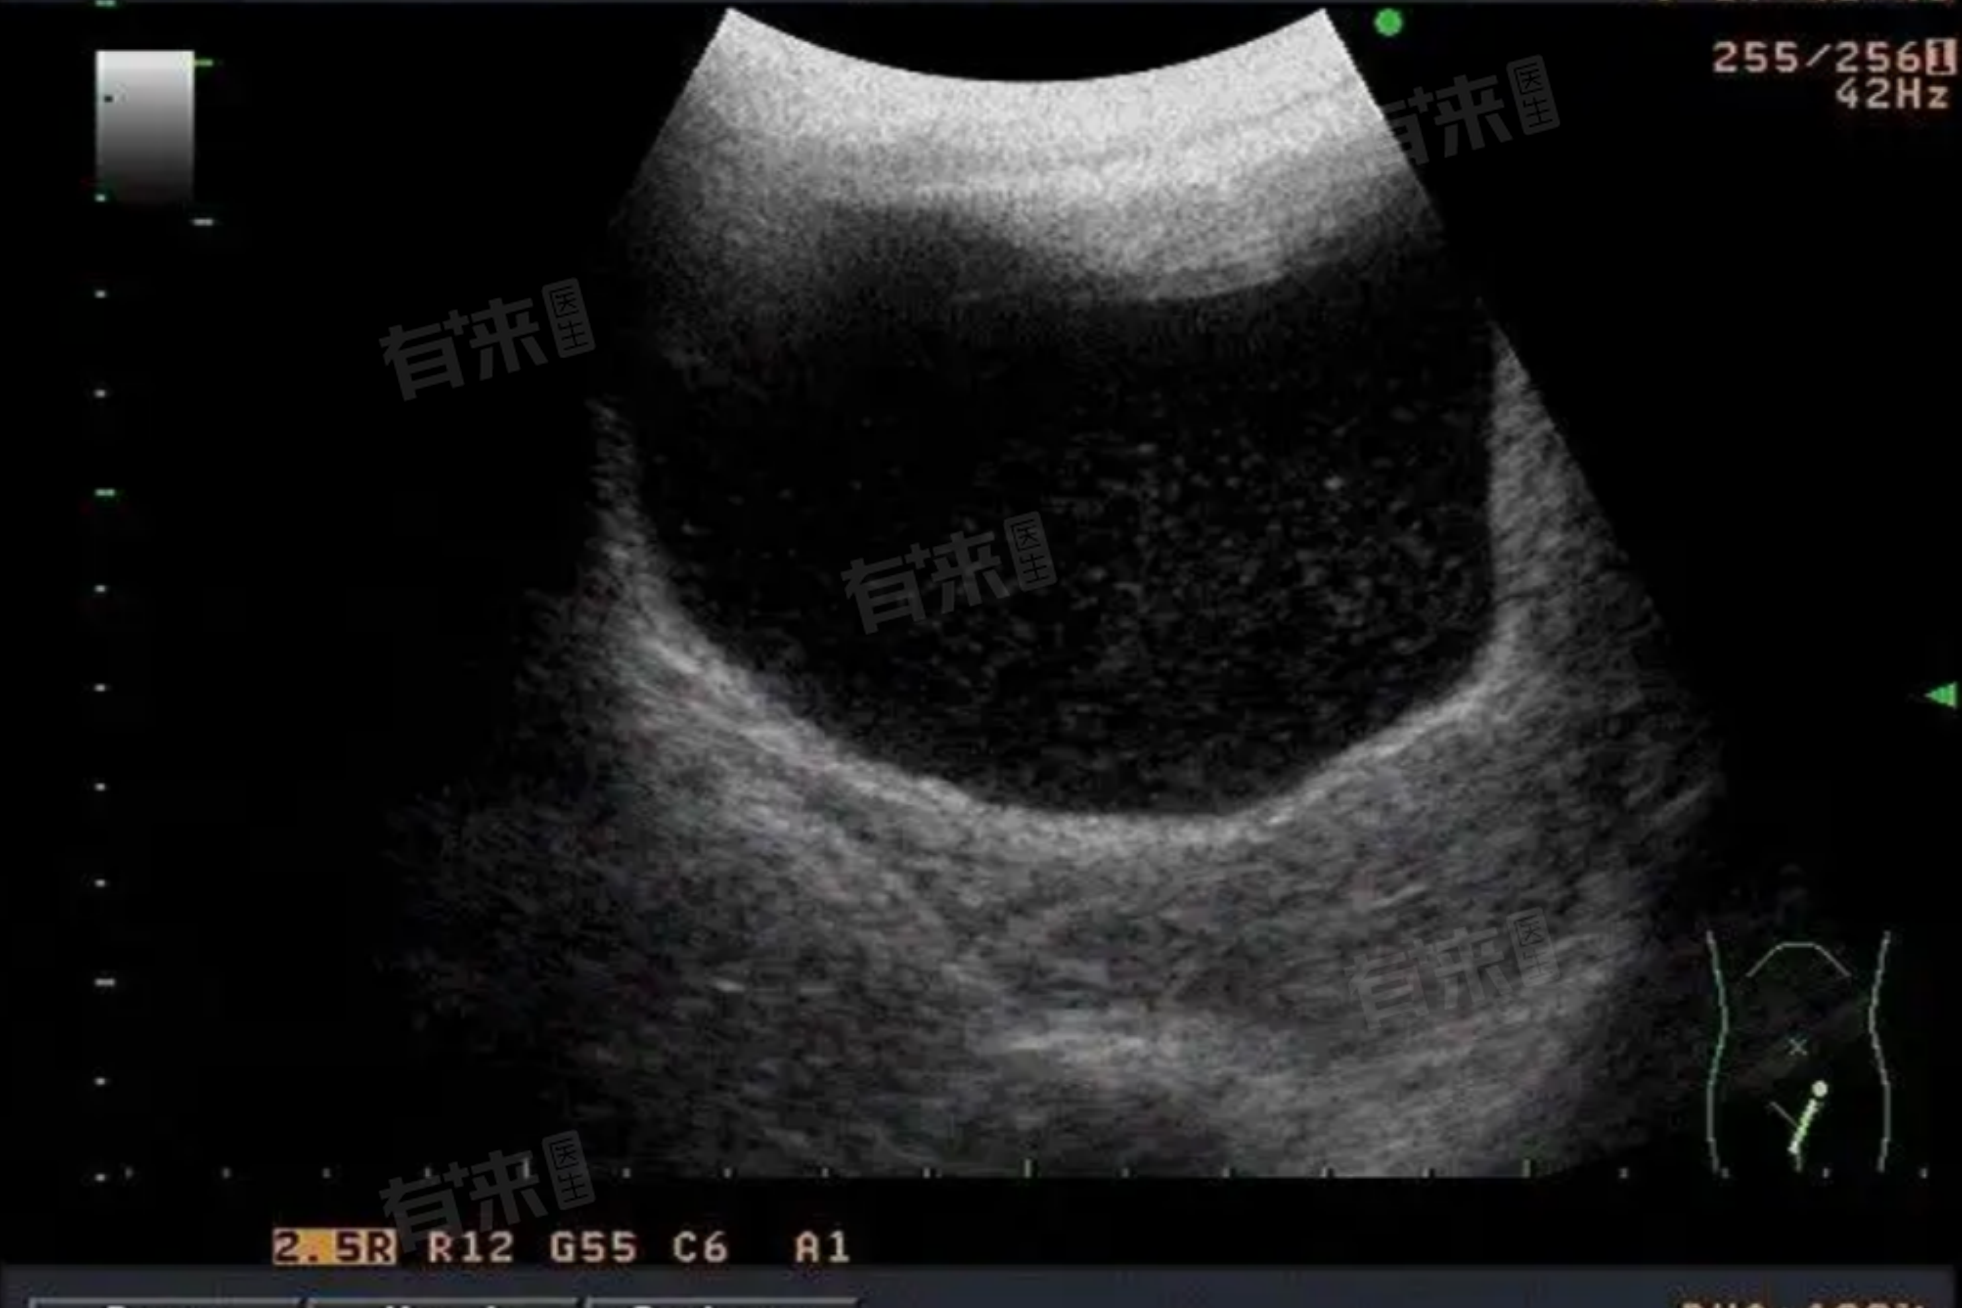

- 对于女性来说,彩超可以检查子宫的形态、大小、内膜厚度等,评估卵巢的储备功能,排查是否存在子宫肌瘤、卵巢囊肿等疾病。对于男性来说,彩超可以检查睾丸、附睾、精索等部位,了解精子的生成和运输情况。

- 通过彩超检查,医生可以根据检查结果为备孕夫妇提供专业的建议和指导,如果发现女性存在子宫内膜过薄或过厚、卵巢囊肿等问题,医生可以制定相应的治疗方案,提高怀孕的几率。如果男性存在精索静脉曲张等问题,也可以及时进行治疗。